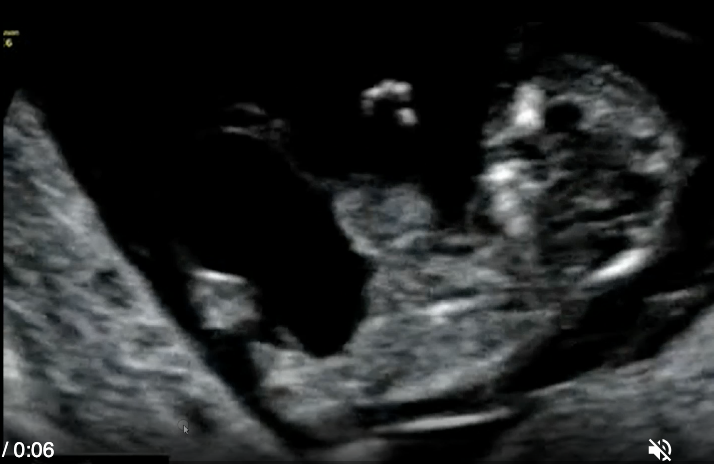

a) umbilical cord cyst

b) placental abruption

c) chorioangioma

d) vasa previa